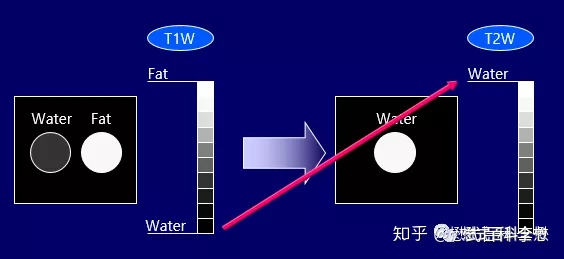

脂肪组织是一种短T1,稍短T2的组织,这个是脂肪组织的特质参数。

如上图所示,是一个头颅的T1WI,非常常见。我们用前面所学的知识。液体(脑脊液)是长T1的,在T1WI中,应该是低信号,是暗的,所以图中,脑脊液是黑色的;而脂肪组织是短T1的,在T1WI中,是高信号,是白的,所以图中,头皮脂肪是亮的。

水(液体)是一种长T1,长T2的组织,这个是液体的特性在参数。

T2越长,在T2WI中,组织的信号强度越高,反映的是图像越白;

T2越短,在T2WI中,组织的信号强度越低,反映的是图像越黑。

脂肪组织是一种短T1,稍短T2的组织,这个是脂肪组织的特质参数。

如上图所示,是一个头颅的T2WI。同前面的分析一样。液体(脑脊液)是长T2的,在T2WI中,应该是高信号,是亮的,所以图中,脑脊液是白色的;而脂肪组织是稍短T2的,在T2WI中,是稍高信号,是白的,所以图中,头皮脂肪也是有点亮的。

所以,无论是在T1WI图像,还是T2WI图像,脂肪组织都是亮的,反映在图像上都是白的。那么很多老师会说,在T2WI上,液体也是白的,脂肪也是白的,我们怎么判断呢?

液体(水),在T1WI上是黑的(暗的),在T2WI上是白的(亮的);

脂肪组织,在T1WI上是亮的,在T2WI上也是亮的;